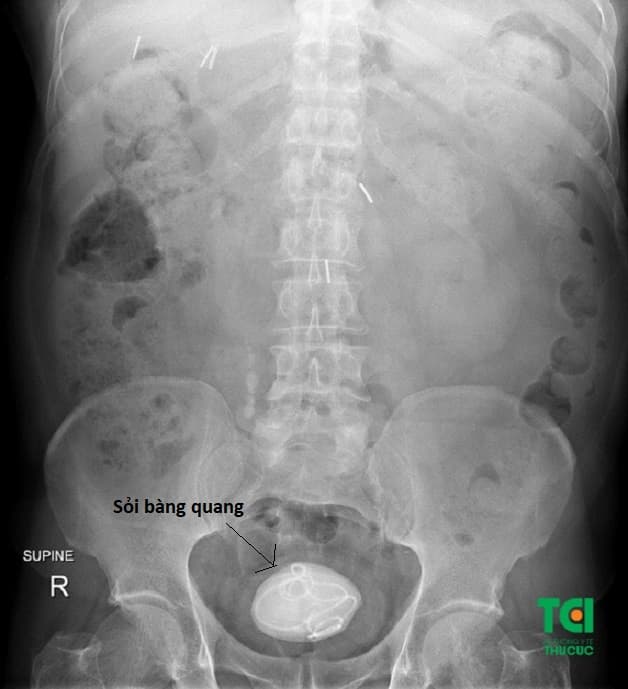

Sỏi bàng quang là sỏi nằm tại bàng quang (bọng đái) của người bệnh mà không được tống xuất ra bên ngoài